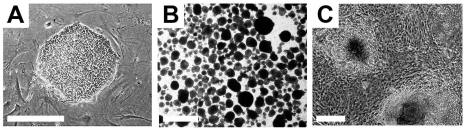

Pluripotent hESCs maintain specific morphological and molecular properties that are shared by the majority of hESC lines. Morphologically, single hESCs have an enlarged nucleus and distinct nucleoli. In culture, proliferating hESCs form compact cell colonies of spherical cells (Figure 2). Under differentiation conditions, these colonies lose their compact morphology and are distinguished by the appearance of flattened cells at the edges as differentiating cells begin to migrate out of the colony. Spontaneous differentiation of hESCs in culture can be controlled with regular supplementation of fresh growth medium [17].

Figure 2. Typical undifferentiated and differentiating hESCs in culture. (A) A compact colony of proliferating pluripotent hESCs can be seen when cultured in defined medium on mouse embryonic fibroblasts. (B) Floating hEBs observed at 3 days after induction of differentiation. (C) Differentiating tissues, including cardiomyocytes, appear within adherent cultures at 48 hours after plating hEBs onto a gelatin-coated culture dish. Bar, 25 μm.